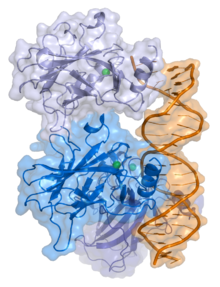

Ao longo do ciclo celular, existem diversos pontos de controlo que só são ultrapassados se não forem detetados erros no genoma. Quando são detetados erros, algumas proteínas produzidas pelos genes supressores tumorais são capazes de bloquear o ciclo celular, nesses pontos. Uma dessas proteínas é codificada pelo gene TP53 ou simplesmente p53 localizado no braço curto do cromossoma 17 (17p13.1) que possui 20 kilobases (kb) e é composto por 11 exões, sendo denominada de TP53 ou p53 (tumor protein p53). Esta fosfoproteína, identificada pela primeira vez na década de 70, com peso molecular aproximado de 53 kiloDaltons (kDa) desempenha um papel muito importante no controlo da proliferação celular, quer parando a progressão do ciclo celular em G1/S para permitir a reparação em casos de lesões do ADN, quer induzindo a apoptose (morte celular de uma forma programada), em resposta a lesões mais extensas. Desta forma, evita a proliferação de células anormais, potencialmente cancerígenas.

Esquema tridimensional da proteína p53 (azul) e do ADN (laranja).

Esquema tridimensional da proteína p53 (azul) e do ADN (laranja).

Quando o gene p53 sofre mutações, a proteína p53 pode deixar de ser funcional não sendo capaz de interromper a divisão celular nem promover a reparação do ADN, as células com o ADN danificado continuam a dividir-se descontroladamente, o que leva à formação de tumores. De facto vários estudos científicos referem a associação de diversos tipos de cancros em humanos a mutações no gene p53, e algumas já foram reportadas.

Dada a importância deste gene supressor tumoral, considerado o “guardião” do genoma humano, bem como a proteína que codifica, têm sido amplamente estudados pela comunidade científica e existem atualmente milhares de publicações sobre o p53, mas ainda há muito por conhecer.

Os trabalhos publicados acerca deste gene e respetiva proteína revelaram muitos dos princípios subjacentes à carcinogénese humana como as diferenças essenciais entre um oncogene e um gene supressor tumoral, a relação entre exposições ambientais e cancro, etc. As conclusões destas investigações, acrescidas ao facto da inativação do p53 ser essencial para a formação da maioria das neoplasias malignas em humanos, tornou a proteína p53 um alvo excecionalmente valioso para a pesquisa básica e aplicada.